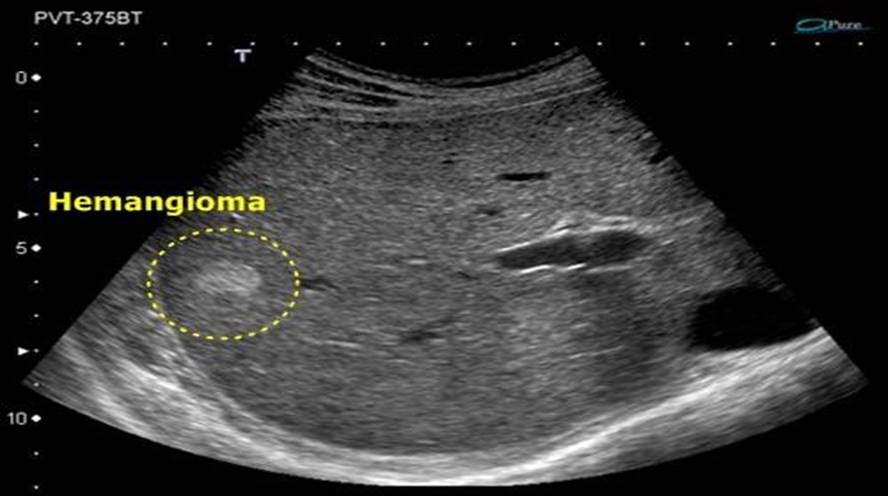

Ultrasound Image of Hemangioma

• USS: echogenic spot, well demarcated.